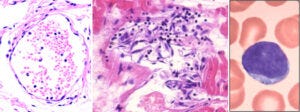

10. A crack in the wall of the aorta, lined by clusters of lymphocytes, leading to aortic rupture

On the left, a section through the wall of an aorta. This picture is taken at an even lower magnification than the one before; the lymphocytes now appear as just a cloud of tiny blue specks. To the left of this blue cloud, we see a vertical crack running through the tissue. Such a crack is also visible macroscopically in the excised specimen of an aorta shown on the right.

The aorta is the largest blood vessel of the body. It receives the highly pressurized blood ejected by the left ventricle of the heart, and it is thus exposed to intense mechanical stress. If the wall of the aorta is weakened by inflammation, as it is here, then it may crack and rupture. Aortic rupture is normally quite rare, but Prof. Burkhardt found multiple cases in his limited number of autopsies. Some of the affected aortas were also shown to have expressed the spike protein.

11. Healthy heart muscle tissue, and lymphocytic myocarditis

In Slide 7, we saw that heart muscle cells strongly expressed the spike protein after vaccine injection. Here, we see the consequences. The picture on the shows a sample of healthy heart muscle tissue, with regularly oriented and aligned heart muscle fibres. On the right, we see a heart muscle sample from one of the autopsies. The muscle fibres are disjointed and disintegrating, and they are surrounded by invading lymphocytes. Burkhardt found myocarditis in multiple of his deceased patients.